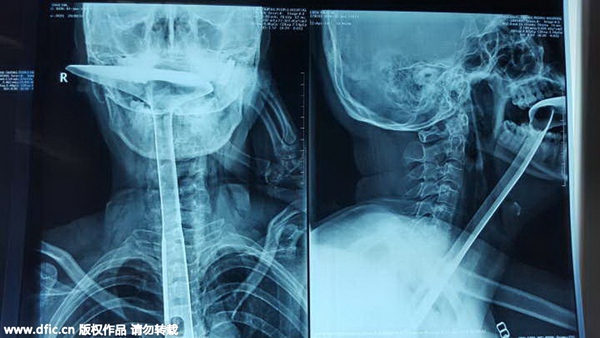

The X-ray picture shows a spetula stuck in the woman's throat. [Photo/IC] |

A woman who shoved a 30-centimeter spetula down her throat stunned doctors with her extraordinary act in Humen county, Dongguan city, Guangdong province, reported South Metropolis Daily on Wednesday.

At first, she used her fingers but they were too short to unblock her throat. Then she chose chopsticks to stick into her throat. After breaking three chopsticks that way, she turned to a spetula and put the handle right into her throat. She soon felt it was impossible to breathe and that's when she went to the hospital for help.

The strange case made the doctors wonder if the woman was suffering from mental illness. But, surprisingly, she appeared to be perfectly sane. Doctors had to cut 20 centimeters out of 25 centimeters of her esophagus since it was badly damaged.